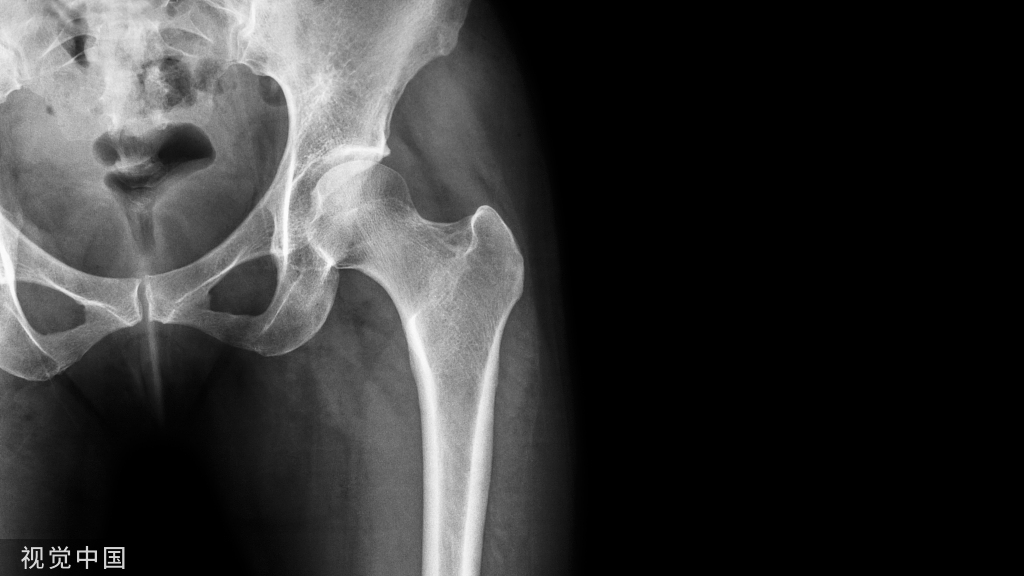

2005年,Ostrum等针对股骨近端髓内钉进钉点位置进行解剖学研究,分别从大转子顶点、大转子顶点偏内2~ 3mm及偏外2~3mm三个位置进钉,结果发现从大转子顶点进针会有轻度的髋内翻,从大转子顶点偏外进钉会造成髋外翻,并且在操作过程中会加大骨折端间隙,因此,认为以大转子顶点偏内侧为最佳进钉点。2011年,Streubel等应用股骨近端髓内钉模板,在50例健康人的髋关节正位片上定位进钉点,测量结果为进钉点距大转子顶点平均偏内3mm(内16mm~外8mm),其中70%的进钉点位于大转子顶点偏内。

2009年,Haidukewych认为股骨近端髓内钉进钉点应在大转子顶点稍偏内侧,由于臀部较大体积的软组织和手术者偏外的操作轨迹,大转子开口在扩髓插钉过程中往往逐渐向外侧扩大成椭圆形,这就可能导致髓内钉的放置位置偏外,相应的就会引起头颈骨块内翻、在股骨头内打入的拉力螺钉位置偏上、髓内钉挤压外侧壁、出现撑开效应等。2013年,Tao等认为,在大转子顶点偏内(约5mm)进钉,即使形成逐渐向外扩大的椭圆形骨洞,也与髓内钉的外偏角比较适合(图5)。

图5 箭头:大转子顶点稍偏内;阴影区:扩髓后偏外形成的正确孔道。

曾有推荐大转子偏外的位置作为最佳进针点,理由是其可避免损伤髋关节和支持带动脉,但目前研究显示这一推荐理由并不确切。因此,我们认为在正面观上以大转子顶点稍偏内(< 5 mm)为进钉点的最佳选择。